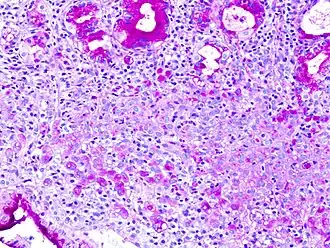

Signet ring cell, as seen in a case of colon adenocarcinoma with mucinous features, showing a tumor cell with a vacuole of mucin. H&E stain.

In histology, a signet ring cell is a cell with a large vacuole. The malignant type is seen predominantly in carcinomas. Signet ring cells are most frequently associated with stomach cancer,[1] but can arise from any number of tissues including the prostate,[2] bladder, gallbladder,[3] breast, colon,[4] ovarian stroma and testis.[5]

The name of the cell comes from its appearance; signet ring cells resemble signet rings. They contain a large amount of mucin, which pushes the nucleus to the cell periphery. The pool of mucin in a signet ring cell mimics the appearance of a finger hole and the nucleus mimics the appearance of the face of the ring in profile.

A significant number of signet ring cells, generally, are associated with a worse prognosis.[6][7]